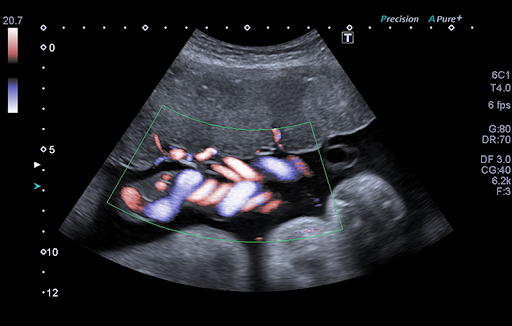

ADF - Advanced Dynamic Flow™* позволяет визуализировать мельчайшие кровеносные сосуды и регистрировать кровоток с непревзойденной точностью и детализацией.

Volume Imaging* Suite включает в себя полный набор режимов обработки изображений (рендеринг поверхности, Multiview и MPR), что позволяет получать большой объем данных при уменьшении времени, требуемого для проведения обследования.